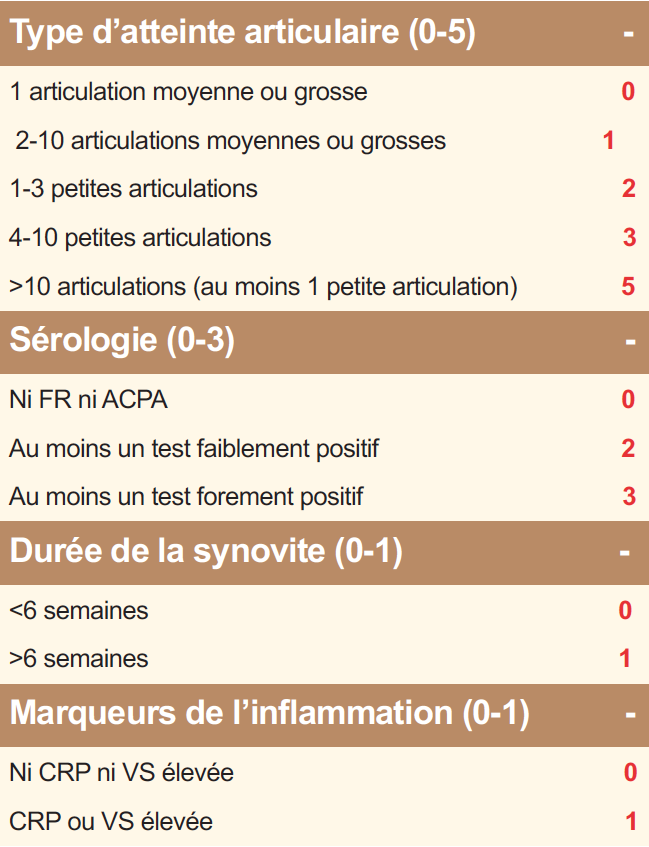

Tableau 1. Critères ACR/EULAR2010 de classification de la polyarthrite rhumatoïde. Le diagnostic de PR est posé si le score est ≥ 6.